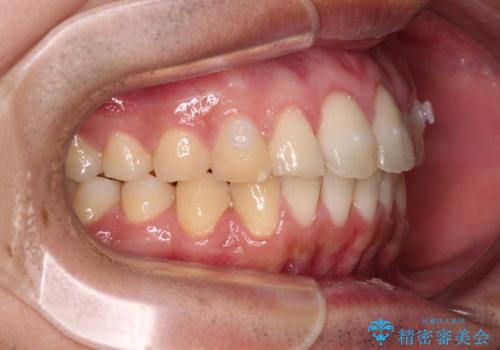

- 上下前歯のデコボコと、それに伴う出っ歯を気にして来院された患者様です。

インビザラインによる上下歯列の側方拡大と後方移動、IPR(歯と歯の間を削る)にるスペースの獲得により歯列を整えることとしました。

歯と歯の間を削ることでうまくスペースコントロールでき、また、毎日22時間以上しっかりとマウスピースを装着していただいたので、スムーズに治療が進みました。

治療途中で転勤となり、遠方からの通院となったため、来院間隔空いてしまいましたが、2年間で終えることができました。